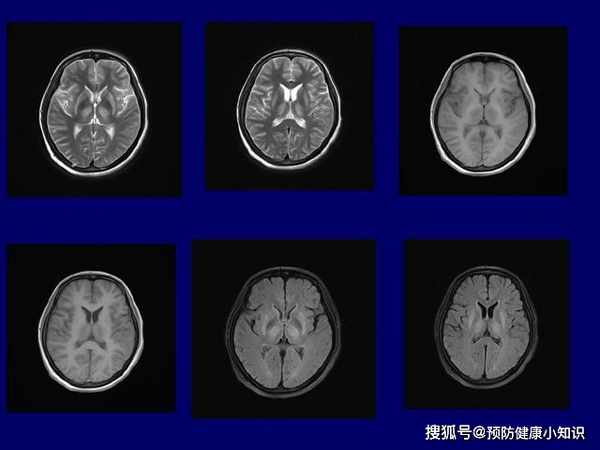

(2)頭顱CT或MRI

可以發現病人的腦損傷情况,對治療有一定的參攷價值。